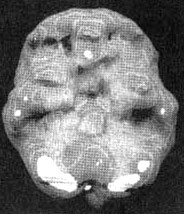

Мозг Роба. Результаты сканирования SPECT

Трехмерное изображение — активный мозг, вид сверху.

До лечения: обратите внимание на выраженное усиление активности в поясной системе (см. стрелку).